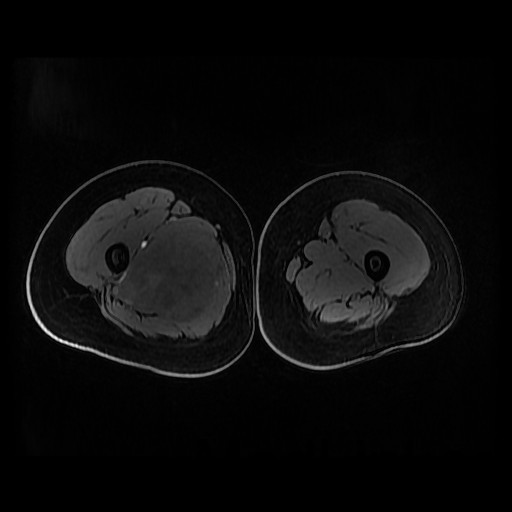

诊断:肺占位性病变(转移瘤?);大腿软组织疾患(右侧大腿肿物) 治疗:入院右下肢MR平扫+增强扫描:右侧大收肌软组织占位性病变,考虑间叶源性恶性肿瘤可能性大,血管源性可能?瘤周多发静脉曲张及侧枝循环形成,建议CT增强扫描进一步检查明确血管情况。遂于声引导下右大腿肿物穿刺活检,病理结果提示:(右大腿肿物)送检穿刺组织,肿瘤细胞形成器官样及腺泡状结构,细胞巢间为纤维性分隔,细胞呈大圆形、多边形,胞质丰富透亮,部分呈嗜伊红色,细胞核大,核分裂象少见,结合临床病史及免疫组化,考虑为腺泡状软组织肉瘤。免疫组化结果(①):CK(-),Vim(-),Ki-67(5%+),HMB45(-),MelanA(-),SMA(+),desmin(-),Myogenin(-),MyoD1(-),S100(-),NSE(部分+),CD56(-)。